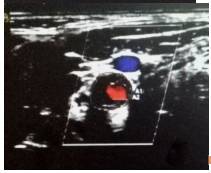

4、心脏彩超

●升主动脉增宽,全心增大,左室壁增厚。

●动脉瓣狭窄(中-重度)并关闭不全(轻度)。

●肺动脉高压(中度)。

●室间隔运动幅度减低。

●左心舒张功能减低。

心脏彩超

●全心增大,左室壁增厚。

●主动脉瓣钙化,狭窄(中-重度)并关闭不全(轻度)。

●三尖瓣大量返流,肺动脉高压(中度)。

●左心功能减低。

●心包腔少量积液。

●左侧胸腔积液。